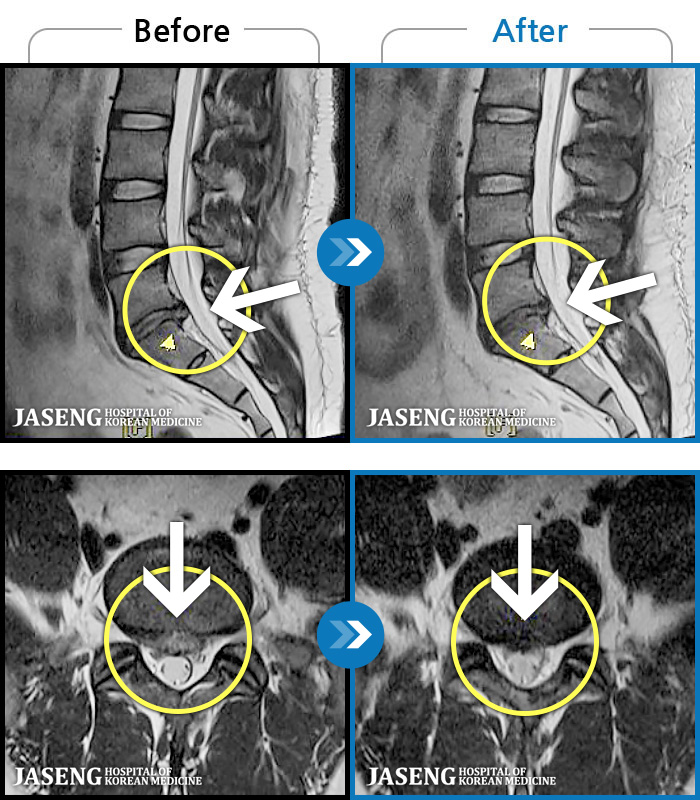

- MRI ġ

MRI ġ

96 MRI ũ ʸ Ȯϼ.